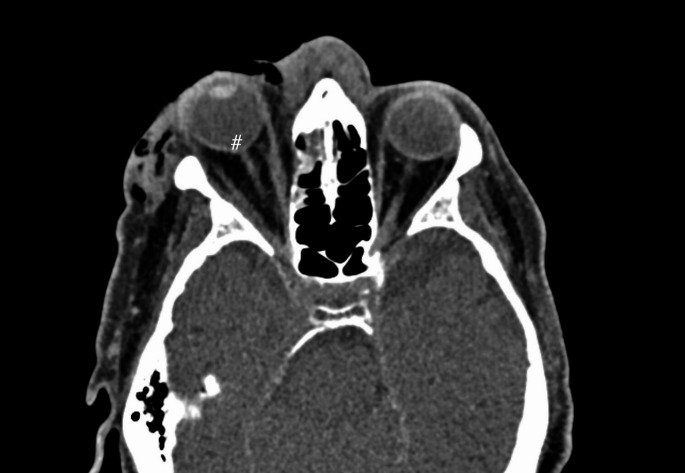

Results: Of the 2149 patients with orbital fractures, 28 (1.3%) presented with acute RBH, including two bilateral haematomas, bringing the total number of RBHs to 30. Specific injury mechanisms were statistically associated with RBH (p = 0.005), with high-energy injuries being the most frequent cause. The prevalence of RBH was higher in bilateral than unilateral fractures (3.1% vs. 1.1%) (p = 0.023). Among unilateral fractures, RBH was most strongly linked to orbital roof and rim fractures. Tenting or tuliped-like appearance on computed tomography and absence of pupillary light reflex were more common in patients with permanent vision loss. Type of surgical approach did not affect visual outcome.

Conclusion: Acute RBH appears to occur more frequently in patients with orbital fractures than previously reported. Clinicians managing facial fractures need to be trained to diagnose RBH promptly and identify indicators of potential vision loss, particularly tenting on radiological images and changes in pupillary reflex.